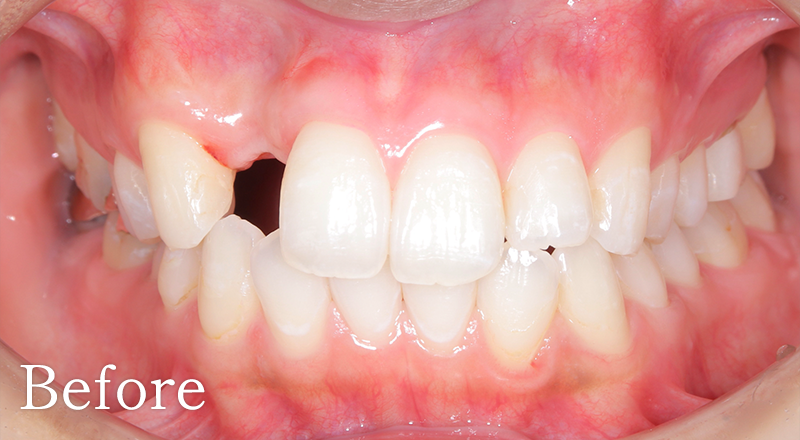

CASE2

骨格2級患者に対し、審美と機能の両立を図り治療を行なった1症例

主訴 右上のブリッジがよく外れる

治療内容 上犬歯インプラント、GBR、咬合再構成、上顎前歯部歯冠長延長術、セラミック治療

治療期間 約2年

費用 診断料:22万円(税込)

右上犬歯インプラント埋入手術:27.5万円(税込)

GBR:11万円(税込)

セラミック補綴:22万円(税込)

セラミック治療:11万円(税込)×18本